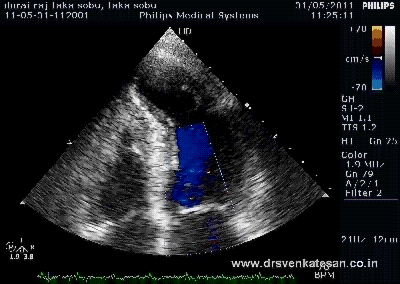

- A meticulous echocardiography

- Hard parameters like pulmonary artery diastolic pressure and pulse pressure